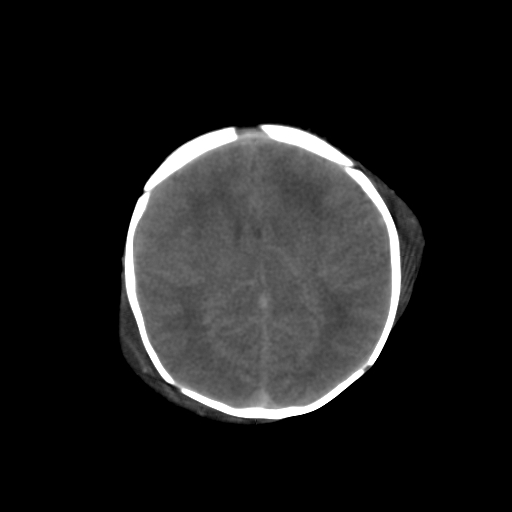

男,3天,患儿为剖腹产,生后嗜睡、拒乳。

1)考虑hie。2)sah?。3)右侧颞顶枕部及左侧颞顶部头皮血肿。

1、右侧颞顶枕部及左侧颞顶部头皮血肿。2、第五第六脑室。3、新生儿,脑白质密度还算可以,也无蛛血,不考虑hie。

脑室系统及脑沟裂闭塞,弥漫性脑密度减低,支持考虑hie,建议复查。右侧颞顶枕部及左侧颞顶部头皮血肿,另不除外胼胝体发育不良,复查